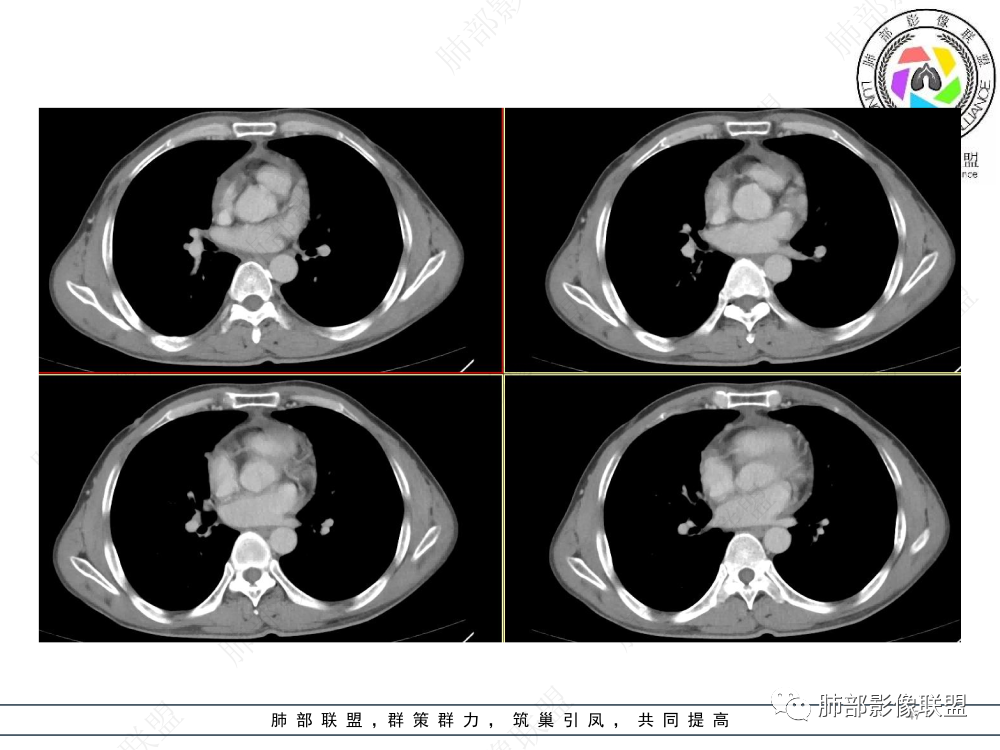

2.影像表现:前上纵隔较大肿块,密度不均,形态不规则,边界不清,有结节样突起,脂肪间隙显示不清。病灶侵犯左无名静脉及上腔静脉,其中左无名静脉闭塞(胸背部侧支循环明显,亦表明回流受阻)。增强后轻中度不均强化。坏死边界欠清晰。可见心包积液,提示心包受侵犯。右侧上叶及纵隔胸膜下结节影,疑胸膜肺转移可能。胸骨柄后缘皮质不完整,疑骨质破坏(未提供骨窗及矢状位图像)。左锁骨上可见肿大淋巴结。

胸腺癌:病灶边界不清,骨骼及血管受侵破坏,胸膜、肺及心包受侵转移等首先想到胸腺癌。胸腺癌最常见病理类型为鳞癌,占70-79%。预后较差,50-65%初诊时伴肺转移,极少伴重症肌无力。影像:胸腺鳞癌形态不规则,易坏死,范围大,坏死区边缘常模糊。

胸腺瘤:胸腺瘤大多边界较清楚。边界模糊或心包侵犯可见于B3型胸腺瘤和癌,但胸腺瘤罕见远处转移、淋巴结转移和纵隔大血管侵犯。

淋巴瘤:体积常较大,常见常在10cm以上,相对低密度结节样堆砌感比较明显,对待骨骼、血管等结构相对“温和”,所谓“血管漂浮”、“肉包骨”则较为常见。病理类型几乎只见于:经典HD、大B细胞淋巴瘤,前驱T淋巴母细胞瘤。实验室检查LDH可升高。初诊时罕见钙化,罕见胸膜受侵。有坏死也常常边界清楚或呈囊变样外观,可伴纵隔、锁骨上淋巴结肿大。